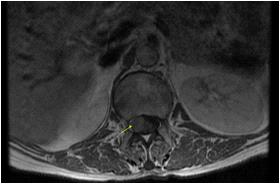

We found a strong positive correlation between abnormal EEG and abnormal Neuroimaging with Correlation coefficient of 0.902, (P- Value 0.0138) but almost no correlation found between normal EEG with normal Neuroimaging (Figs 1-4).

About 23% of patients with adult onset first seizure has metabolic derangement and the most common etiology was Dyselectrolytemia. The most common Central Nervous System (CNS) Infection as detected by CSF study was viral meningoencephalitis followed by Tuberculous Meningitis. The most common CNS lesion detected by CT studies as well as by MRI Brain was infarction and ring lesion, the two Neuroimaging studies corroborated in 75.38% of Seizure patients. Abnormal discharge in EEG found in34% cases. In majority patients EEG report was normal. EEG abnormality was more common in patients with Focal Seizure rather than GTCS patients. Thus, the most common etiology of first Seizure onset at adult age over 18 years were metabolic derangements (16.92%), CNS Infection or Inflammation (15.38%) and intracerebral Space occupying lesion (15.38%), usually ring lesion, tumors and Metastasis. Idiopathic Seizure found in 7.69% patients. The Correlation between abnormal Neuroimaging and abnormal EEG is strongly positive and statistically significant (P -Value = 0.013) but the same is not true in cases of normal Neuroimaging and normal EEG findings.